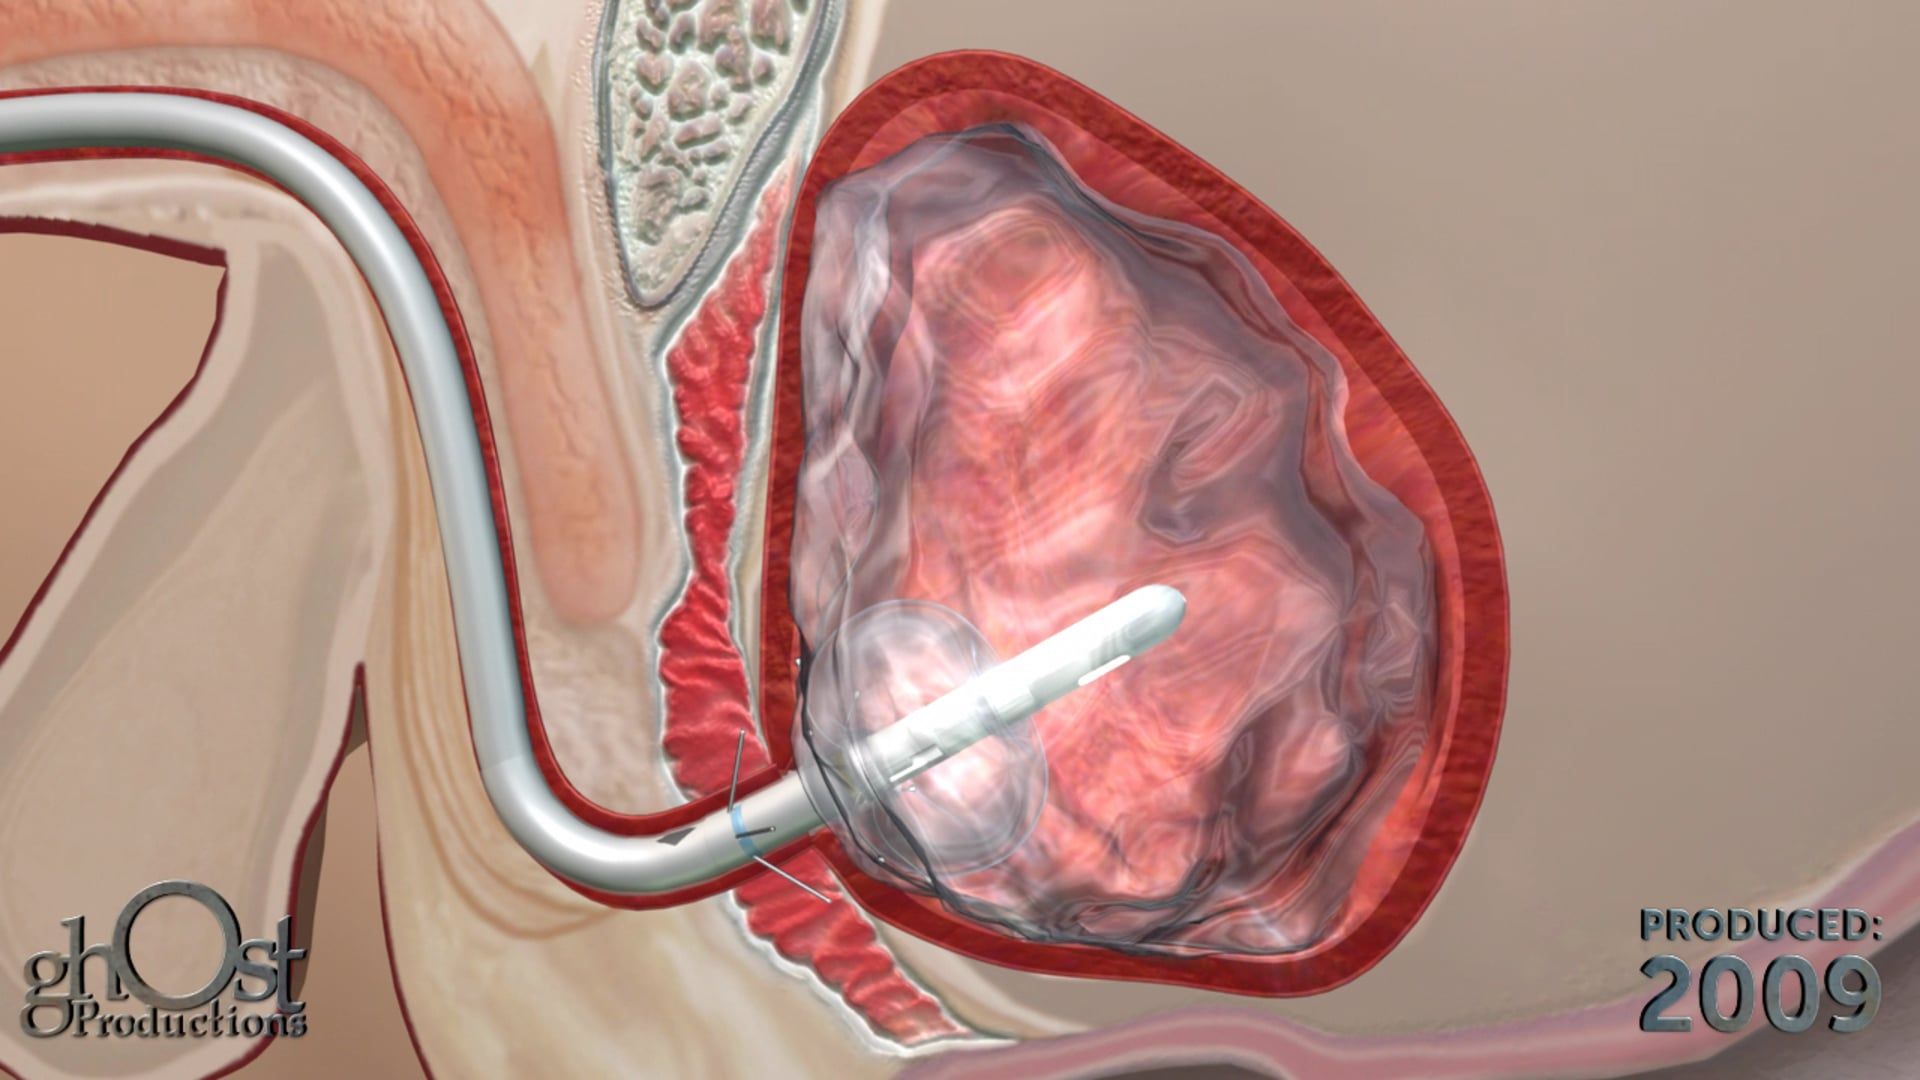

AMS partnered with Ghost Productions, a medical animation and graphics company, to create a series of animations and medical graphics that effectively communicated the benefits of their products. Ghost Productions worked closely with AMS's team to understand the mechanism of action of each product and create a visual representation of the process.

the animations and medical graphics produced by Ghost Productions proved to be instrumental in helping AMS effectively communicate the benefits of their products to their target audience. The visual aids helped potential customers and physicians understand the mechanism of action of each product and the benefits of using them to treat urological and gynecological conditions.